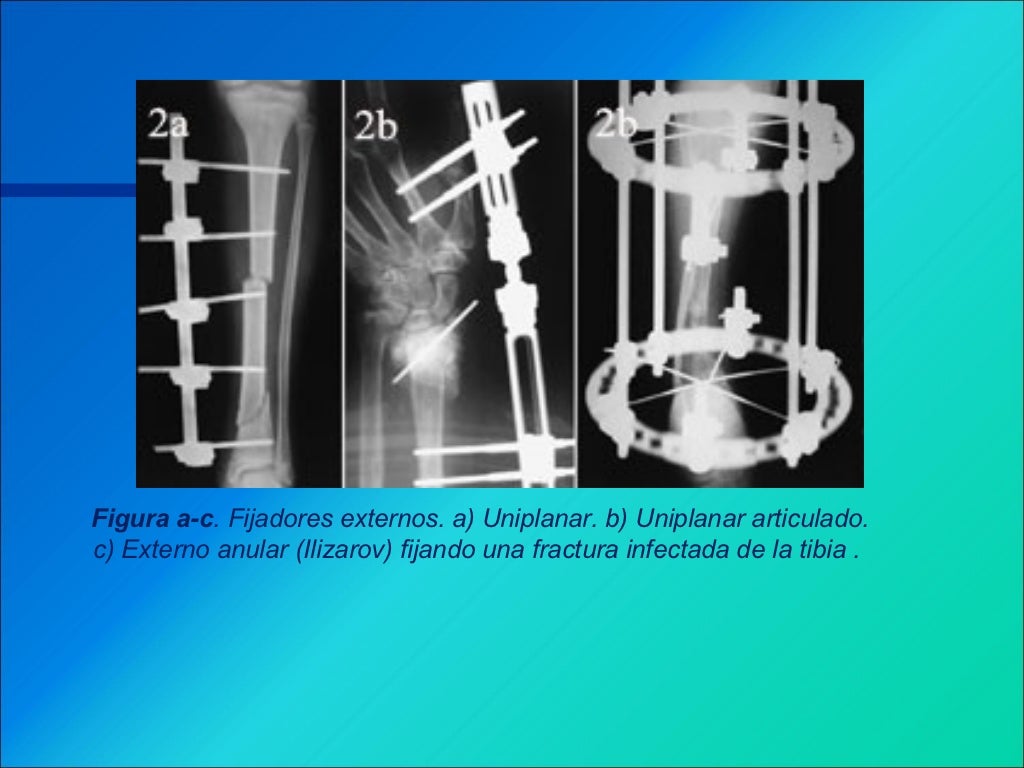

WebEl tiempo de recuperación de la osteosíntesis dependerá del manejo que se tomo y las características de la fractura. Como regla general una fractura consolida (pega) en. WebLa localización del dolor es un mal indicador del valor de la extracción del material de osteosíntesis. Tal vez habría que ofrecer la retirada a más pacientes. Esto. WebEn intervenciones quirúrgicas para la fijación de fracturas óseas se usan placas, clavos o tornillos para tratarlas. El uso de estos está indicado para mantener el.